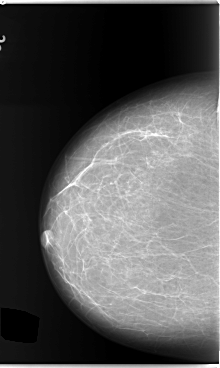

C_0132_1.LEFT_MLO

LEFT_MLO LINES 5920 PIXELS_PER_LINE 3784 BITS_PER_PIXEL 12 RESOLUTION 50 OVERLAY

RIGHT_MLO LINES 5880 PIXELS_PER_LINE 3768 BITS_PER_PIXEL 12 RESOLUTION 50 NON_OVERLAY